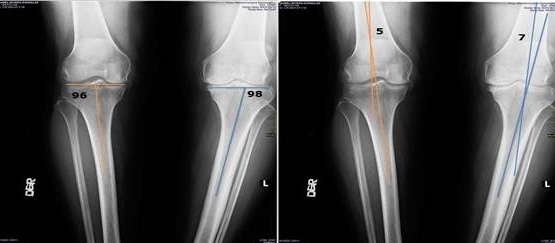

La Artroscopia permite tratar lesiones articulares mediante pequeñas incisiones, reduciendo el tiempo de recuperación y las complicaciones. Este procedimiento se aplica principalmente en rodillas, hombros y otras articulaciones, con resultados efectivos y seguros.

Antes

Después